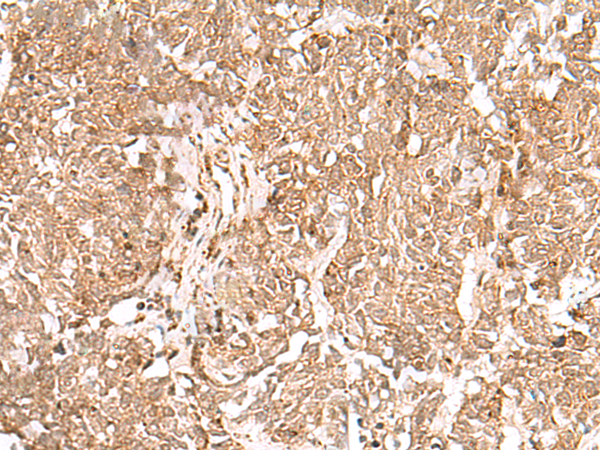

IHC positive control: |

Human lung cancer |

IHC Recommend dilution: |

50-300 |